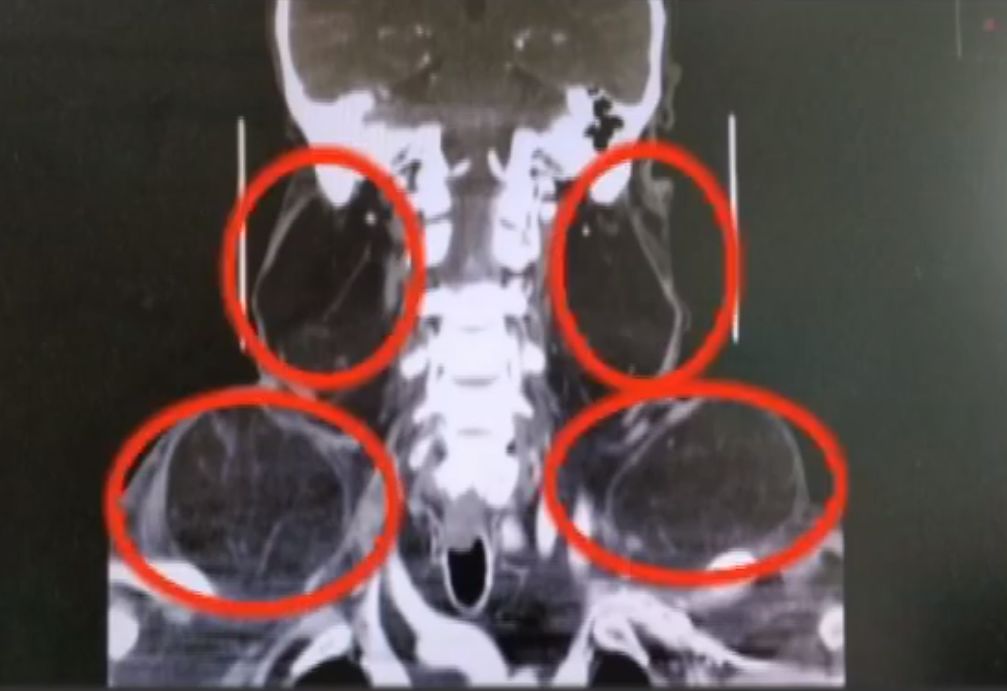

这是李老伯做手术之前的照片,李老伯的脖子位置有两个苹果大小的囊肿,两边肩膀位置也分别隆起同样大小囊肿。今年五月中旬,李老伯试着来到安顺市302医院。

那么李老伯到底患的到底是什么怪病呢?原来谢医生从李老伯的CT报告,再结合李老伯胡的酗酒史,判断李老伯患上的是罕见的马卡龙疾病。

谢医生说:这是世界罕见的病,在世界上有明确报道的有两百多例,在国内报道比较少,所以说非常罕见,这个病主要分布在地中海地区,而且是多发于中老年男性,长期酗酒可能是主要病发原因。